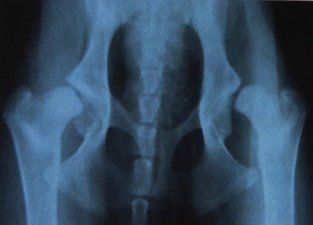

Vergelijk deze foto's eens en u kunt zeer waarschijnlijk zelf ook het verschil zien:

Op foto 3 ziet u zeer slechte heupen. De heupkom is nauwelijks aanwezig en het is duidelijk dat deze hond een zeer goede bespiering moet hebben om de heupen nog ongeveer op de goede plaats te houden!